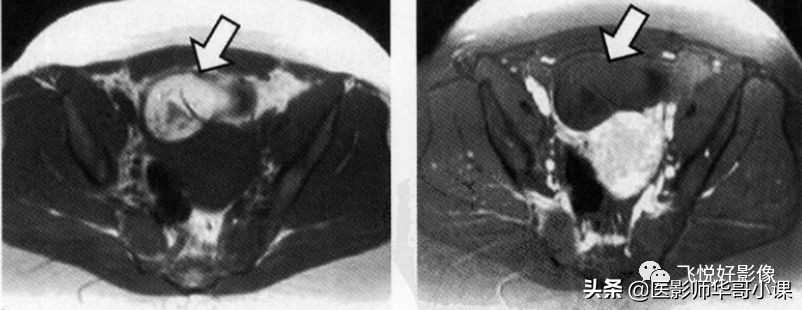

前后扫描两组序列,一组T2W序列,一组压脂序列,可以通过压脂,判断病灶内含有脂肪,为临床鉴别诊断提供依据。

我们举一个常见例子,在做盆腔压脂序列时候,有时候会发现图像对角线部分会有一些信号不均匀及丢失等现象,这种伪影叫 四极电场伪影 。

该伪影产生的原因主要是人体在磁场内产生的涡流(内在固有效应),导致B1场分布不均匀,主要以横断面为主。

那么针对这种伪影,解决方法也很简单,换一种压脂方法。